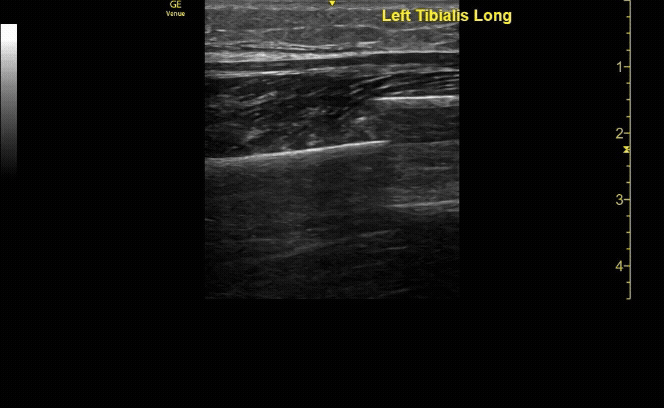

Unaffected tibia in transverse view.

c/o Santiago Tovar, MD